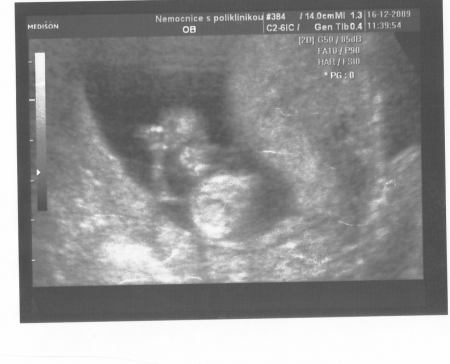

Plod o velikosti 62 mm ve 13. týdnu těhotenství (12+4). Na všech snímcích je snadno rozeznatelná lebka s obličejovou částí, páteř plodu a jeho dolní končetiny.

Autoři: Texty na základě zdroje www.babyonline.cz, vlastní praxe a znalostí zpracovala MUDr. Jarmila Halová, doplnil a upravil MUDr. Ondřej Šimetka, přednosta Porodnicko-gynekologické kliniky FN Ostrava, kde byly rovněž pořízeny ultrazvukové snímky, autor: MUDr. M. Pětroš. Poslední korekturu v srpnu 2024 provedla: MUDr. Veronika Ťápalová (Gynekologicko-porodnická klinika LF MU a FN Brno).